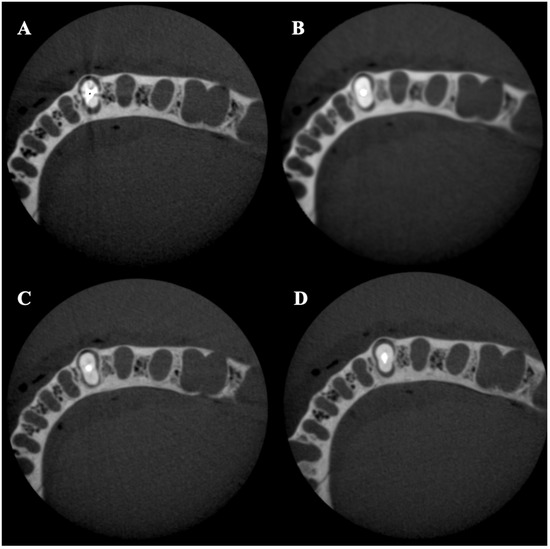

- Fontenele, R.C.; Farias Gomes, A.; Rosado, L.P.L.; Neves, F.S.; Freitas, D.Q. Mapping the expression of beam hardening artefacts produced by metal posts positioned in different regions of the dental arch. Clin. Oral Investig. 2020, 25, 571–579. [Google Scholar] [CrossRef]

- Pinto, M.G.O.; Rabelo, K.A.; Sousa Melo, S.L.; Campos, P.S.F.; Oliveira, L.S.A.F.; Bento, P.M.; Melo, D.P. Influence of exposure parameters on the detection of simulated root fractures in the presence of various intracanal materials. Int. Endod. J. 2017, 50, 586–594. [Google Scholar] [CrossRef]